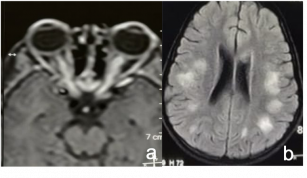

Infantile Haemangioma. a & b) CE MRI (T1 weighted) of brain and orbit- Axial section showing well-defined lesion involving the left orbit with no intraconal extension, involving the medial rectus muscle. It shows heterogeneous enhancement with contrast. c & d) MRI brain and orbit (T2 weighted)- Axial and coronal section, the lesion shows hyperintensity. | |